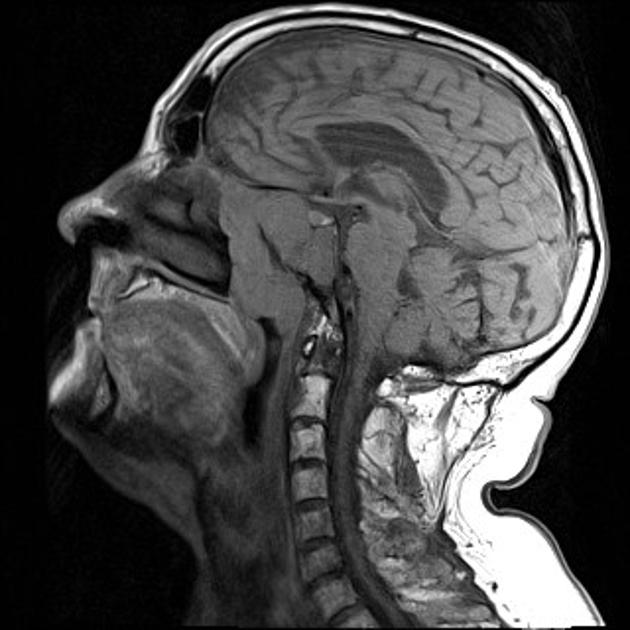

La presencia en plasma de ADN del virus Epstein-Barr tuvo una sensibilidad de 97,1% y una especificidad de 98,6% para el diagnóstico de carcinoma nasofaríngeo, realizado por endoscopía y resonancia magnética. New England Journal of Medicine, 10 de agosto de 2017